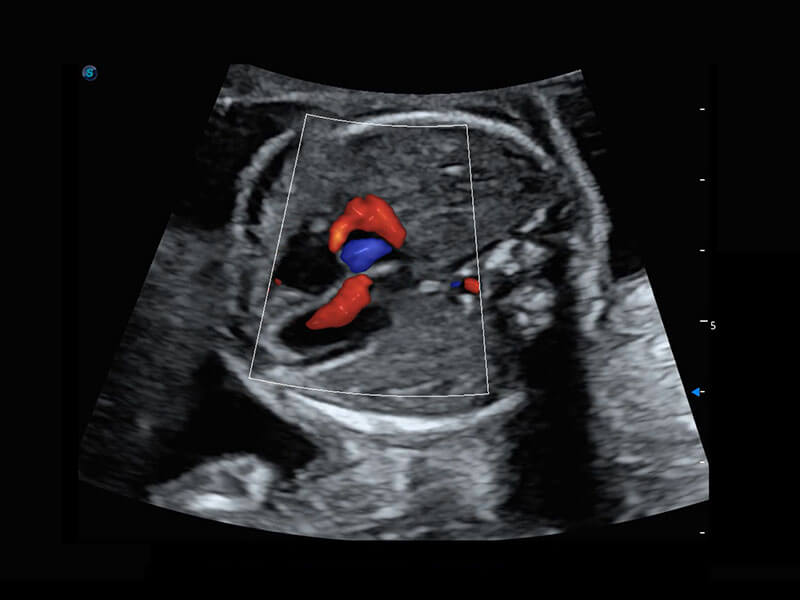

腔内三维-宫内节育器

腔内三维-光影成像